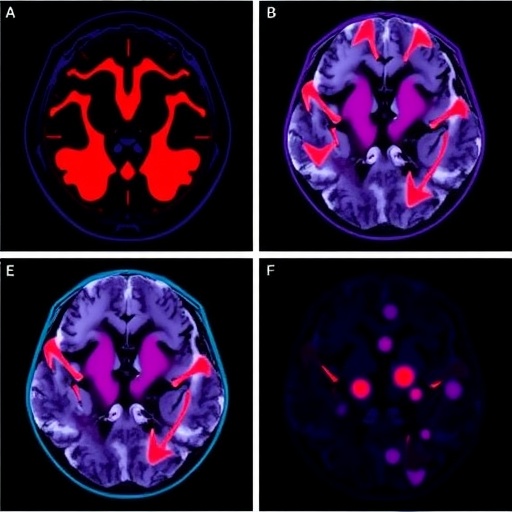

In the relentless quest to conquer glioblastoma, one of the most aggressive and fatal brain cancers, researchers have made a groundbreaking advancement that could redefine personalized cancer therapy. A recent study published in Nature Communications unveils a novel approach centered around the polyclonal expansion of tumor-infiltrating lymphocytes (TILs), harnessing the body’s own immune cells to mount a targeted and multifaceted attack against glioblastoma tumors. This innovative cell therapy strategy may open unprecedented avenues for effective treatment of a malignancy long notorious for its resistance to conventional therapies.

Glioblastoma multiforme (GBM) has presented a formidable challenge in neuro-oncology, primarily due to its highly invasive nature, heterogeneity, and immunosuppressive tumor microenvironment (TME). Previous attempts to employ immunotherapy in GBM have often faltered because the adaptive immune response in the brain is uniquely regulated, and the tumor itself frequently evades immune detection. However, this new research harnesses the polyclonal repertoire of tumor-reactive lymphocytes naturally infiltrating glioblastoma tissues, suggesting a paradigm shift where the immune system’s intrinsic capacity is amplified and redirected for therapeutic benefit.

At the heart of this approach lies the principle of isolating TILs directly from patient tumor samples, followed by their ex vivo polyclonal expansion under conditions that preserve their tumor specificity and effector functions. Unlike monoclonal strategies that rely on single antigen targets and risk immune escape, polyclonal expansion capitalizes on the diverse array of tumor antigens recognized by various T cell clones. This diversity is crucial in GBM, where antigenic heterogeneity and mutational burden complicate targeted therapies.